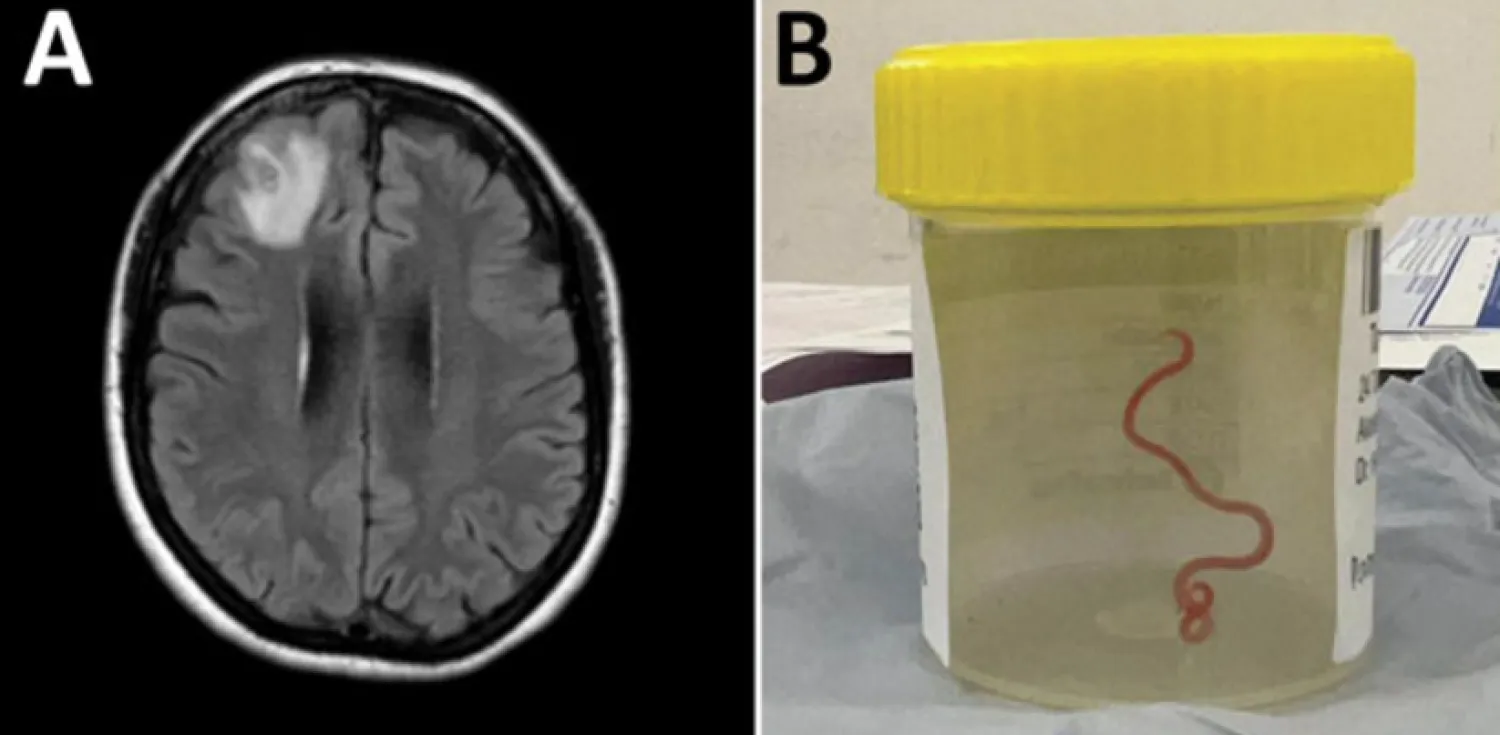

MR taraması yapılan kadında anormal beyin aktiviteleri tespit edilmesi nedeniyle ameliyat olmasına karar verildi.

Ameliyat esnasında doktorlar, kadının beyninden 8 santimetre uzunluğunda ve 1 milimetre genişliğinde canlı solucan çıkardı.

İncelenmesi için laboratuvara gönderilen "Ophidascaris robertsi" adlı solucanın genelde pitonlarda görülen bir parazit olduğu belirlendi.